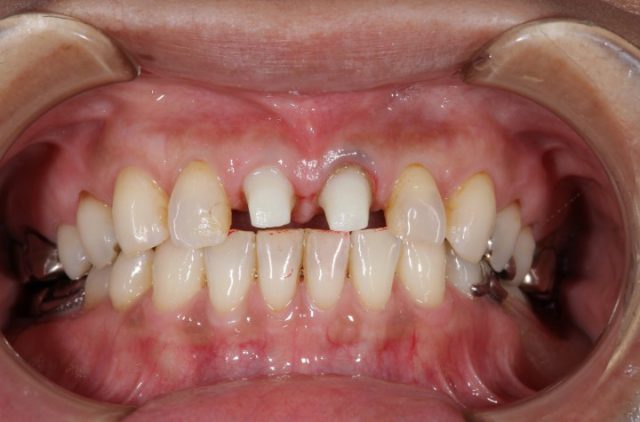

施術前

施術前の画像を見るとそれほど変色している印象を受けることはありませんが、よく見ると前歯の虫歯治療した後の部分の詰め物の変色しています。今回の患者様はこの部分をとても気にされていました。

詰め物を削りやり直したとしてもまた数年後には同じことになるため今回は思い切ってオールセラミックによる施術を選択されました。